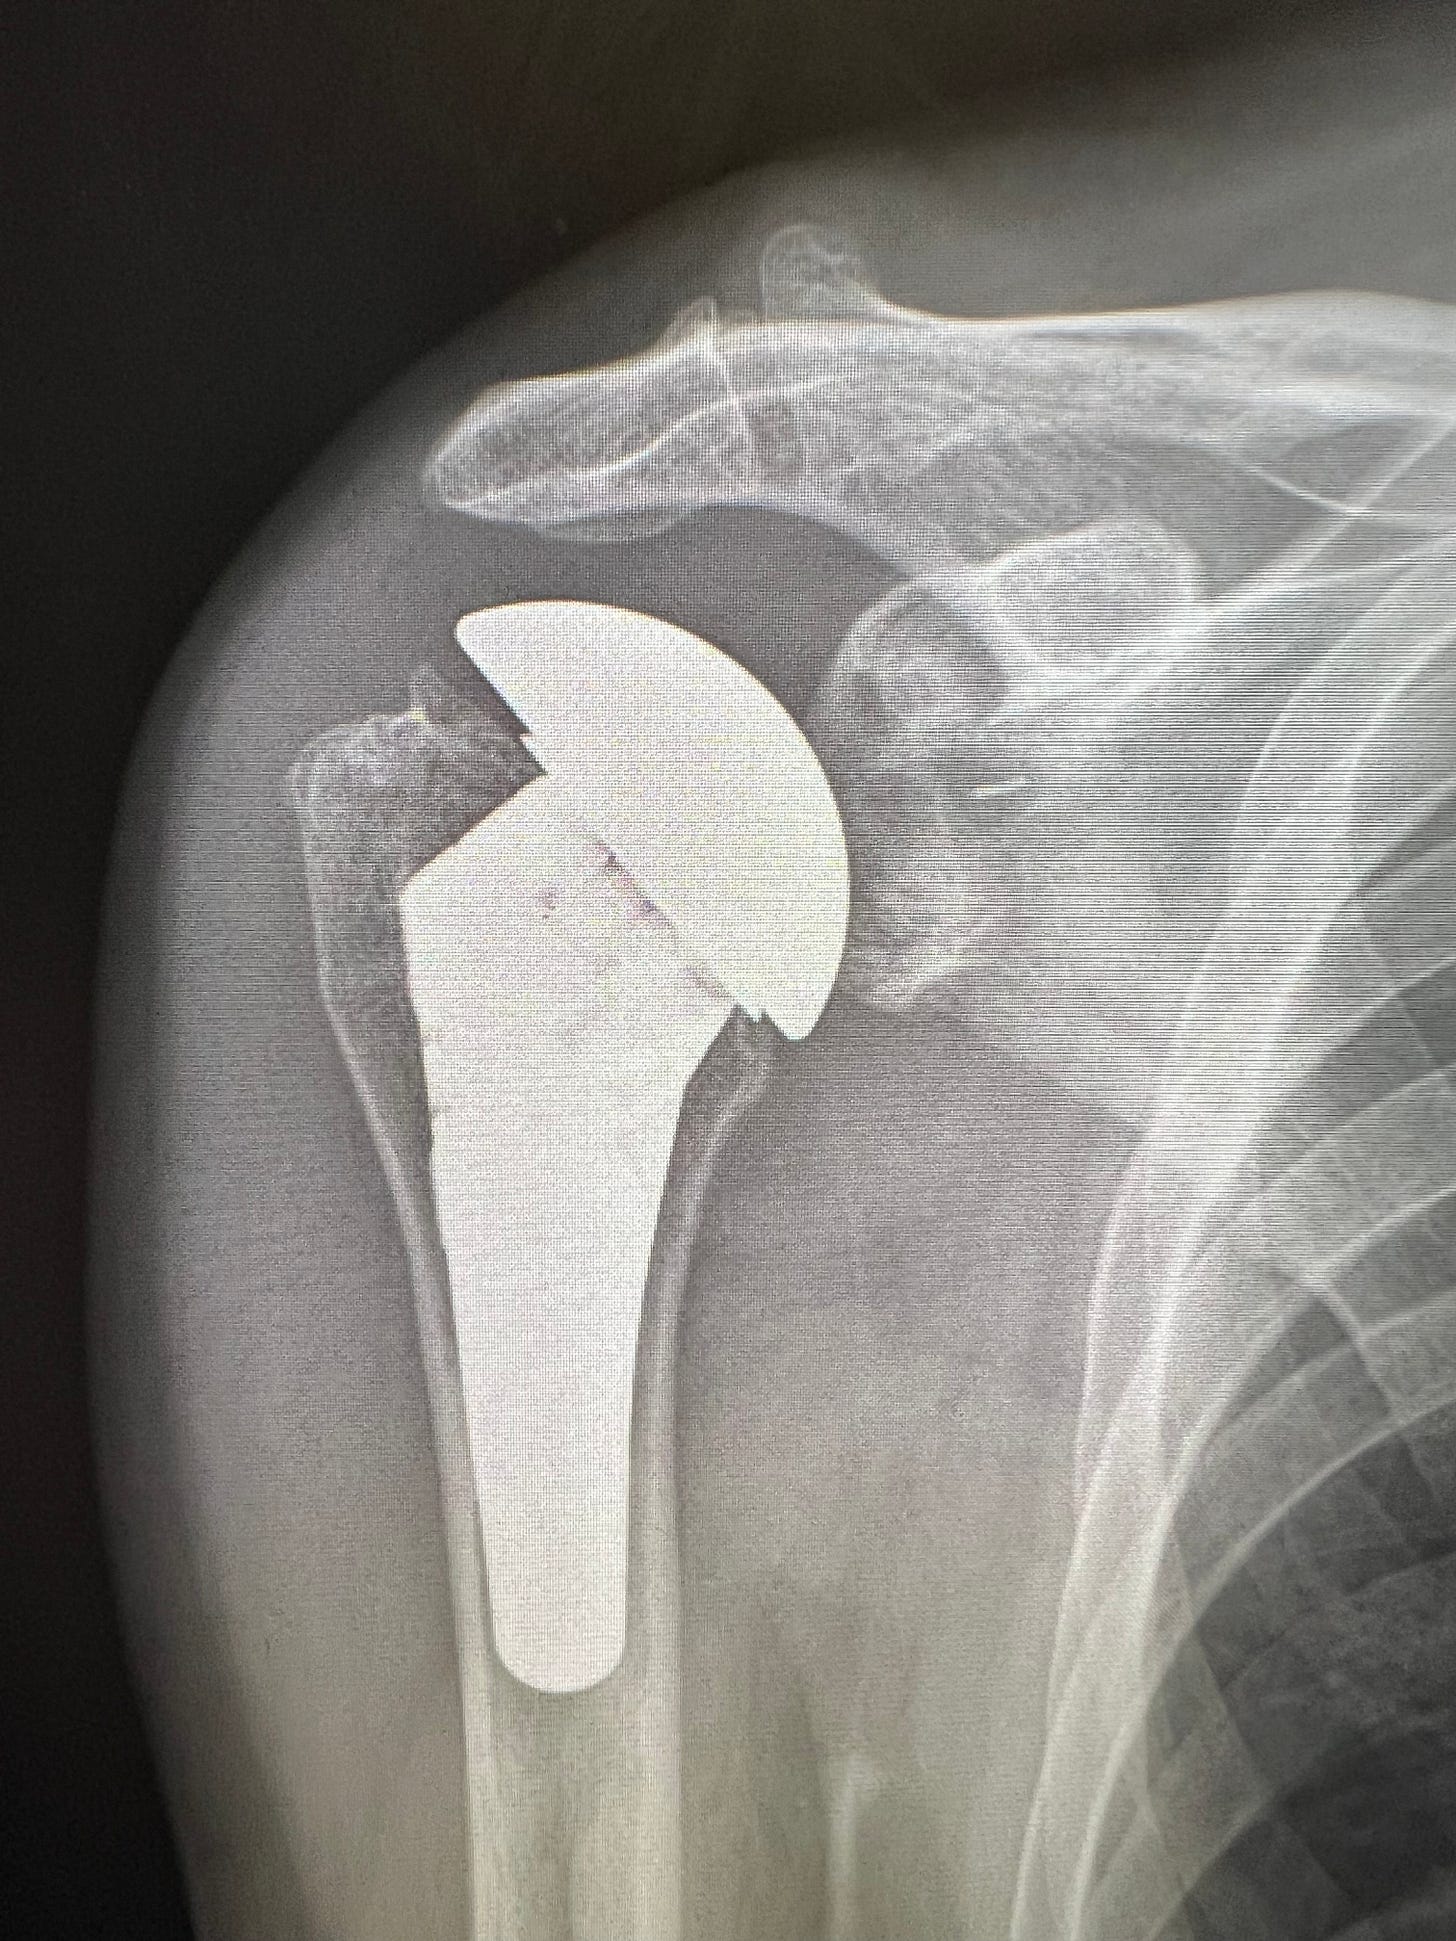

Total shoulder arthroplasty (replacement) has seen an increasing prevalence with technological advancements over the past thirty years. One of the most common questions I encounter in my practice is how new is the shoulder replacement procedure? The consensus from medical and laypeople is that shoulder replacement is a new procedure without long-term data to support its utilization. The shoulder replacement has spanned over 130 years, with the first shoulder replacement performed by French Surgeon Jules Emile Péan in 1893. The patient was a 37-year-old gentleman with advanced tuberculosis. The prosthesis significantly improved his quality of life for 2 years prior to infection, necessitating its removal. The prosthesis is on display at the Smithsonian Institution. Dr. Charles Neer, an American Orthopaedic Surgeon in the 1950’s, developed the Neer I prosthesis, a partial replacement that became standard until his Neer II design in the 1970’s, which addressed the glenoid and became a Total Shoulder. In 1987, my mentor, Dr. Wayne ‘Buz’ Burkhead, developed the Select Modular Shoulder prosthesis, becoming the first modular total shoulder system. Around the same time, in the late 1980’s, Dr. Paul Grammont began developing the reverse Total Shoulder for the treatment of rotator cuff-deficient shoulder arthritis. Since completing my Shoulder and Elbow Fellowship in 2006 with Dr. Burkhead, I have witnessed the technological explosion in total shoulder prosthesis. This has resulted in increased indications and patient outcomes. Harkin et al.’s study from 2025 reveals that surgeons who perform more than 20 total shoulder replacements per year have significantly lower complication rates. Being a Subspecialist in Shoulder and Elbow, I specialize in managing complex shoulder and elbow disorders.